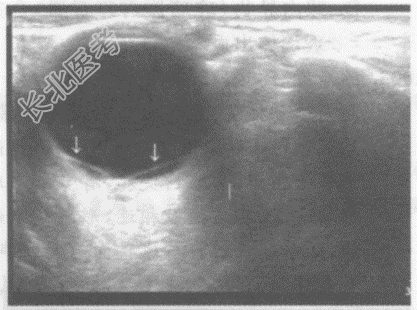

- 单项选择题临床资料:男, 57岁,自诉近视30余年, 近1月右眼视物模糊,眼前阴影遮挡, 视力下降,当地医院诊断糖尿病视网膜痛变。眼科检查: 视力:右0.05、左0.6。眼底右眼窥视较模糊, 视盘边界不清,水肿, 血管走行尚可,视网膜大量散在点片状出血, 火焰状。

超声综合描述:右眼玻璃体暗区内可见带状回声, 其尖端与视盘相连,两边分别与周边球壁相连(箭头所示), 呈“V“形,运动试验、后运动阳性, CDFI:带状回声内可见动脉血流信号, 且与视网膜中央动脉血流信号相延续。